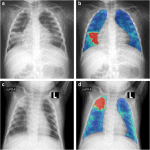

Tắc Động Mạch Phổi | Bài giảng CĐHA

Tắc mạch phổi (Pulmonary Embolims) là hiện tượng tắc ít nhất một động mạch phổi hoặc nhánh động mạch phổi, thường do huyết khối từ tĩnh mạch sâu di chuyển lên. Đây là một bệnh khá thường gặp tuy nhiên khó chẩn đoán vì dễ nhầm với các bệnh khác. Bệnh nhân không được chẩn đoán và điều trị phù hợp có tỷ lệ tử vong lên đến 30%.